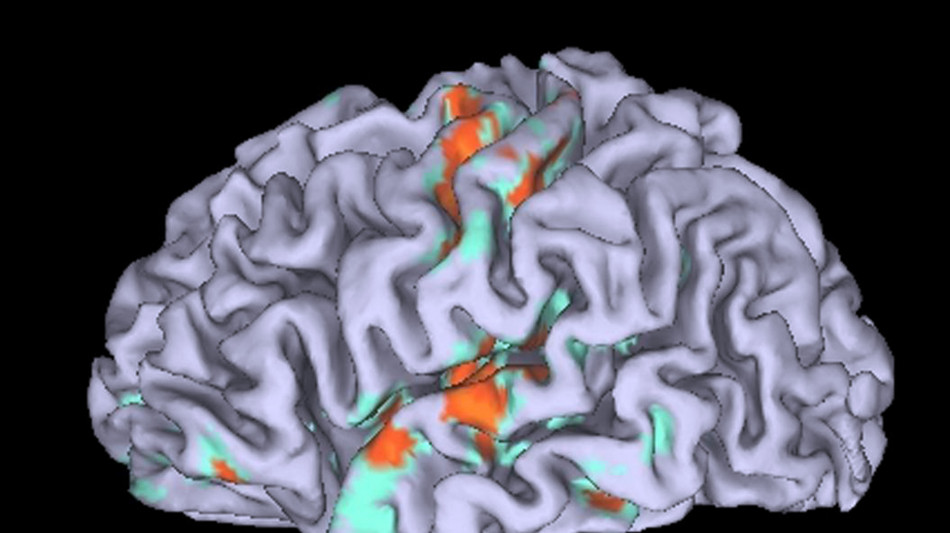

Gli esseri umani hanno imparato da tempo che rallentare la respirazione aiuta a controllare e calmare le proprie emozioni, ma finora era stato impossibile capire il meccanismo alla base di questo legame. Adesso, è stato finalmente identificato il circuito cerebrale che collega il respiro volontario allo stato d'animo di una persona: utilizzando i topi, ricercatori guidati dal Salk Institute di La Jolla in California hanno individuato un gruppo di cellule cerebrali nella corteccia frontale, implicata nella pianificazione di comportamenti complessi, che si collega al tronco encefalico, dove invece vengono controllate azioni vitali come la respirazione. Lo studio, pubblicato sulla rivista Nature Neuroscience, offre nuovi strumenti per poter controllare attacchi di panico, ansia e disturbo da stress post-traumatico. I ricercatori coordinati da Sung Han hanno condotto diversi esperimenti alla ricerca di connessioni tra il centro del tronco encefalico che regola il respiro e altre zone del cervello: hanno così individuato un nuovo circuito, che hanno messo alla prova registrando l'attività cerebrale dei topi durante comportamenti che alterano la respirazione, come annusare, nuotare e bere, e durante situazioni che generavano paura o ansia. I risultati confermano che, quando il circuito è attivo, gli animali risultano più calmi e respirano più lentamente, mentre in situazioni di stress il collegamento diminuisce e la frequenza del respiro si alza. "Voglio utilizzare questi risultati per progettare una sorta di 'pillola yoga'", dice Han. "Può sembrare sciocco, e la traduzione del nostro lavoro in un farmaco commerciabile richiederà anni - aggiunge il ricercatore - ma ora disponiamo di un circuito cerebrale che può diventare un bersaglio terapeutico per rallentare istantaneamente la respirazione e promuovere una stato di calma e tranquillità".